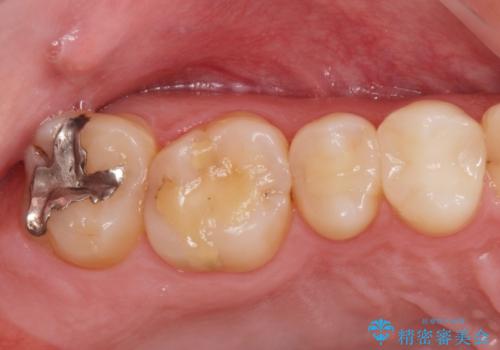

奥の歯に穴が空いている

- 奥の歯に穴が空いているとの事で来院。

拡大鏡下で虫歯を全て除去しゴールドインレーにて治療しました。

- ゴールドインレー 7.7万円費用は治療当時の料金となります